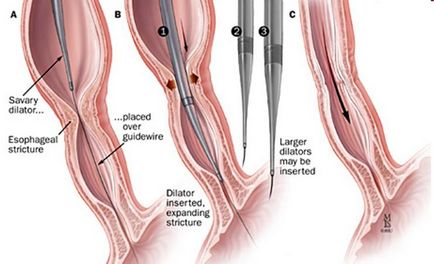

Більш агресивна методика лікування полягає в направленому впливі на тканини в стравоході хворого. Бужування є оперативним втручанням.

За допомогою ендоскопа лікар може розтягувати або розривати кільця ендоскопа і спеціальних розширювачів конусоподібної форми. Вони вставляються в ротову порожнину пацієнта, переміщаються по ендоскоп до кілець. Зазвичай така методика застосовується рідко. Для процедури потрібен досвідчений лікар. Таке лікування може бути розбите на 3 етапи.

Також можна розширювати кільця. Для цього в стравохід вводиться балон, який дозволяє робити дилатацію органу. Після введення балона за допомогою повітря лікар починає збільшувати його обсяг, щоб розширити просвіт.